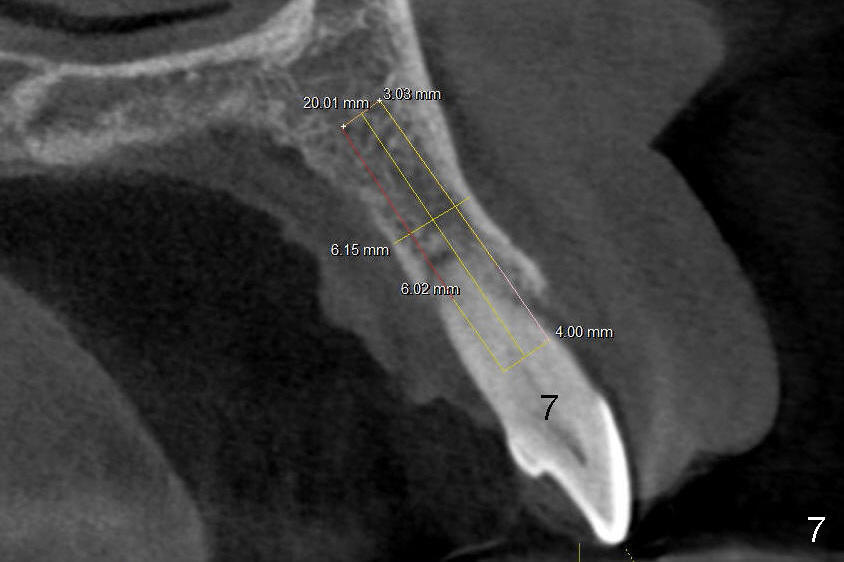

12. Bicon reamers, save bone, later mix with synthetic bone (Osteogen), reamers until 3.0 mm for #7, 3.5 for #6, tap 4.5x20 for 6, then 5x20, possibly 6x20

14. Place implants as palatally as possible. Use Tatum tapered drills if orientation changes unfavorably